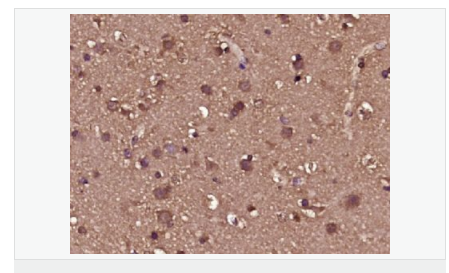

交叉反應(yīng):Rat,Mouse,Human(predicted:Sheep,Rabbit,Horse,Cow,Pig,Dog) 推薦應(yīng)用:IHC-P,IHC-F,IF,ELISA

| 產(chǎn)品應(yīng)用 | WB=1:500-2000 ELISA=1:5000-10000 IHC-P=1:100-500 IHC-F=1:100-500 ICC=1:100-500 IF=1:100-500 (石蠟切片需做抗原修復(fù)) not yet tested in other applications. optimal dilutions/concentrations should be determined by the end user. |